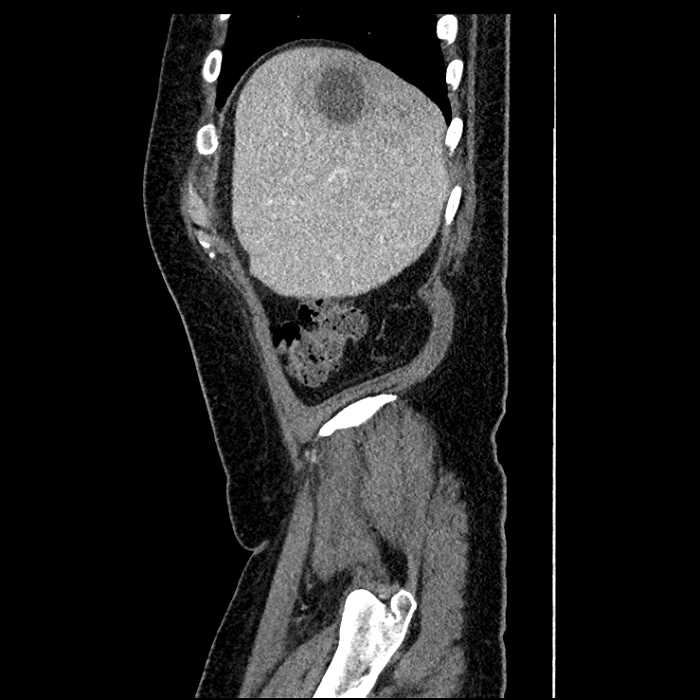

Age: 63

Sex: Male

Indication: Abdominal pain

• Large fluid density structure in hepatic segments 7 and 8 measuring 10 x 7 x 7 cm with internal septation and circumferential ill-defined low density compatible with edema

• Hepatic abscess

Acute sigmoid diverticulitis complicated by a small contained perforation and a large abscess in the right hepatic lobe. Additional small subcapsular abscesses along the anterior margin of the left hepatic lobe.

• The classic CT imaging appearance is a double target sign with internal low density surrounded by an internal enhancing rim (capsule) and a low density external rim (edema)

Hepatic abscess showing the double target sign with low density internally surrounded by a thin inner enhancing rim (red arrow) and ill-defined outer low density rim (yellow arrow). Blue arrow indicates an internal septation. Red arrows: additional smaller subcapsular abscesses. Red arrow: focal contained perforation associated with diverticulitis.